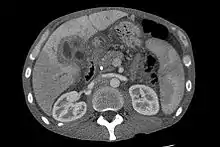

| CT scan of a liver with cholangiocarcinoma | |